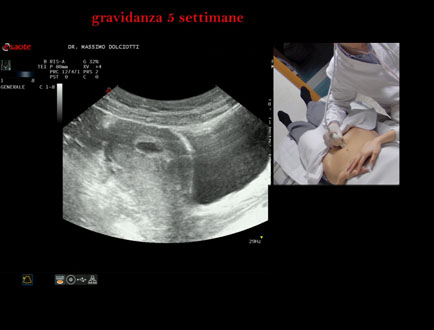

Data inserimento: 06/02/2026

Ecografia del: 28/01/2025

Strumento: Esaote MyLab Eight

Sonda: Convex Multifrequenza 1-8 MHz

Età Paziente: F 28 anni

Motivazione dell'esame: amenorrea.

Commento all'esame: le immagini ed il video documentano la camera gestazionale delle dimensioni di 11 mm e presenza di embrione delle dimensioni di 4,1 - 5,4 mm, con iniziale battito cardiaco.

Conclusioni: gravidanza alla quinta settimana di gestazione (pregnancy in the 5th week of gestation).

In collaborazione: Dr.ssa Marica Manfredi - Ancona, Dr. Ilir Qose - Ancona

Presentazione: Dr. Massimo Dolciotti - Ancona

Elaborazione digitale: Andrea Dini - Ancona